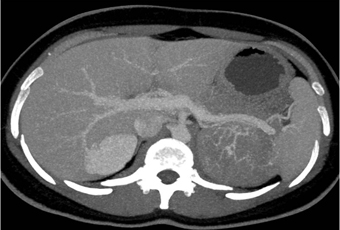

In this patient with symptoms of Cushings Disease the best diagnosis is?

adrenal adenoma

pheochromocytoma

lymphoma

primary adrenal carcinoma